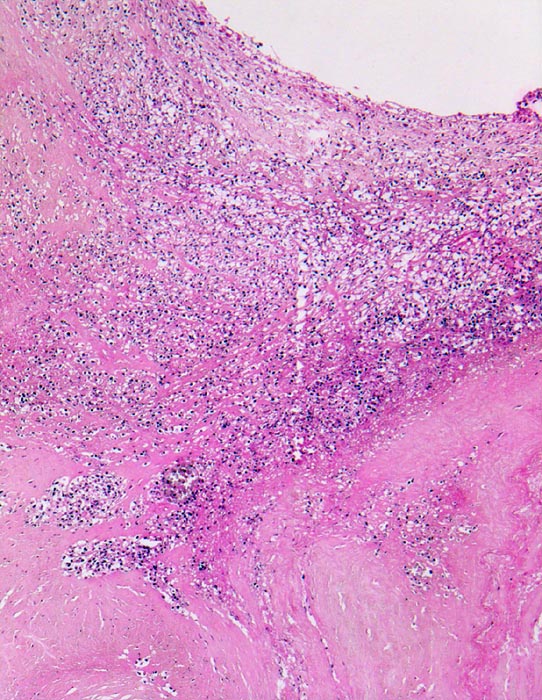

Endocarditis ulcero-polyposa der Aortenklappe

Aortenklappe

In dem Zwickel zwischen noch erhaltener Klappe und Polyp beginnende Granulationsgewebsbildung.

Akut einsetzendes Krankheitsbild mit Fieber, Schüttelfrost, Müdigkeit und Dyspnoe. Blutkulturen wiederholt positiv für Staphylokokkus aureus. Keine Klappenvorschädigung bekannt.

Histologie

50